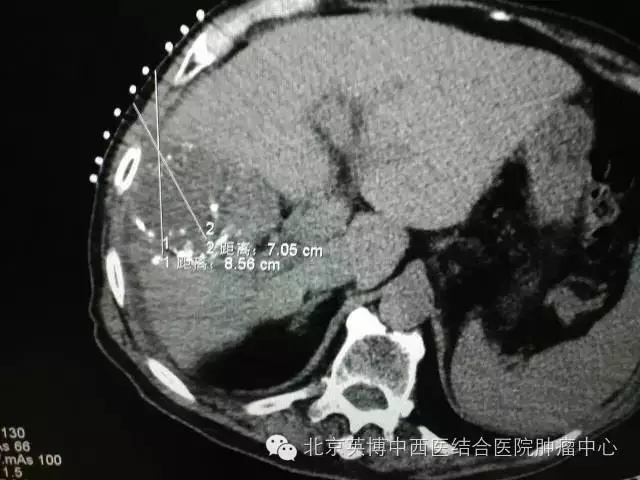

一位82岁的高龄男性,在4月的例行体检中发现肝占位,并于7月份在市内其他医院确诊,后进行过介入治疗一次、放疗25次。因其本人也在医疗系统工作几十年,对于现今的治疗技术和手段的关注度、敏锐度高于常人,当获悉北京英博中西医结合医院特邀原中国医学科学院肿瘤医院原副院长刘伯齐教授亲自来医院开展氩氦刀手术后,慕名治疗,术后效果也确实如他所期,非常明显,未出现任何不良反应。